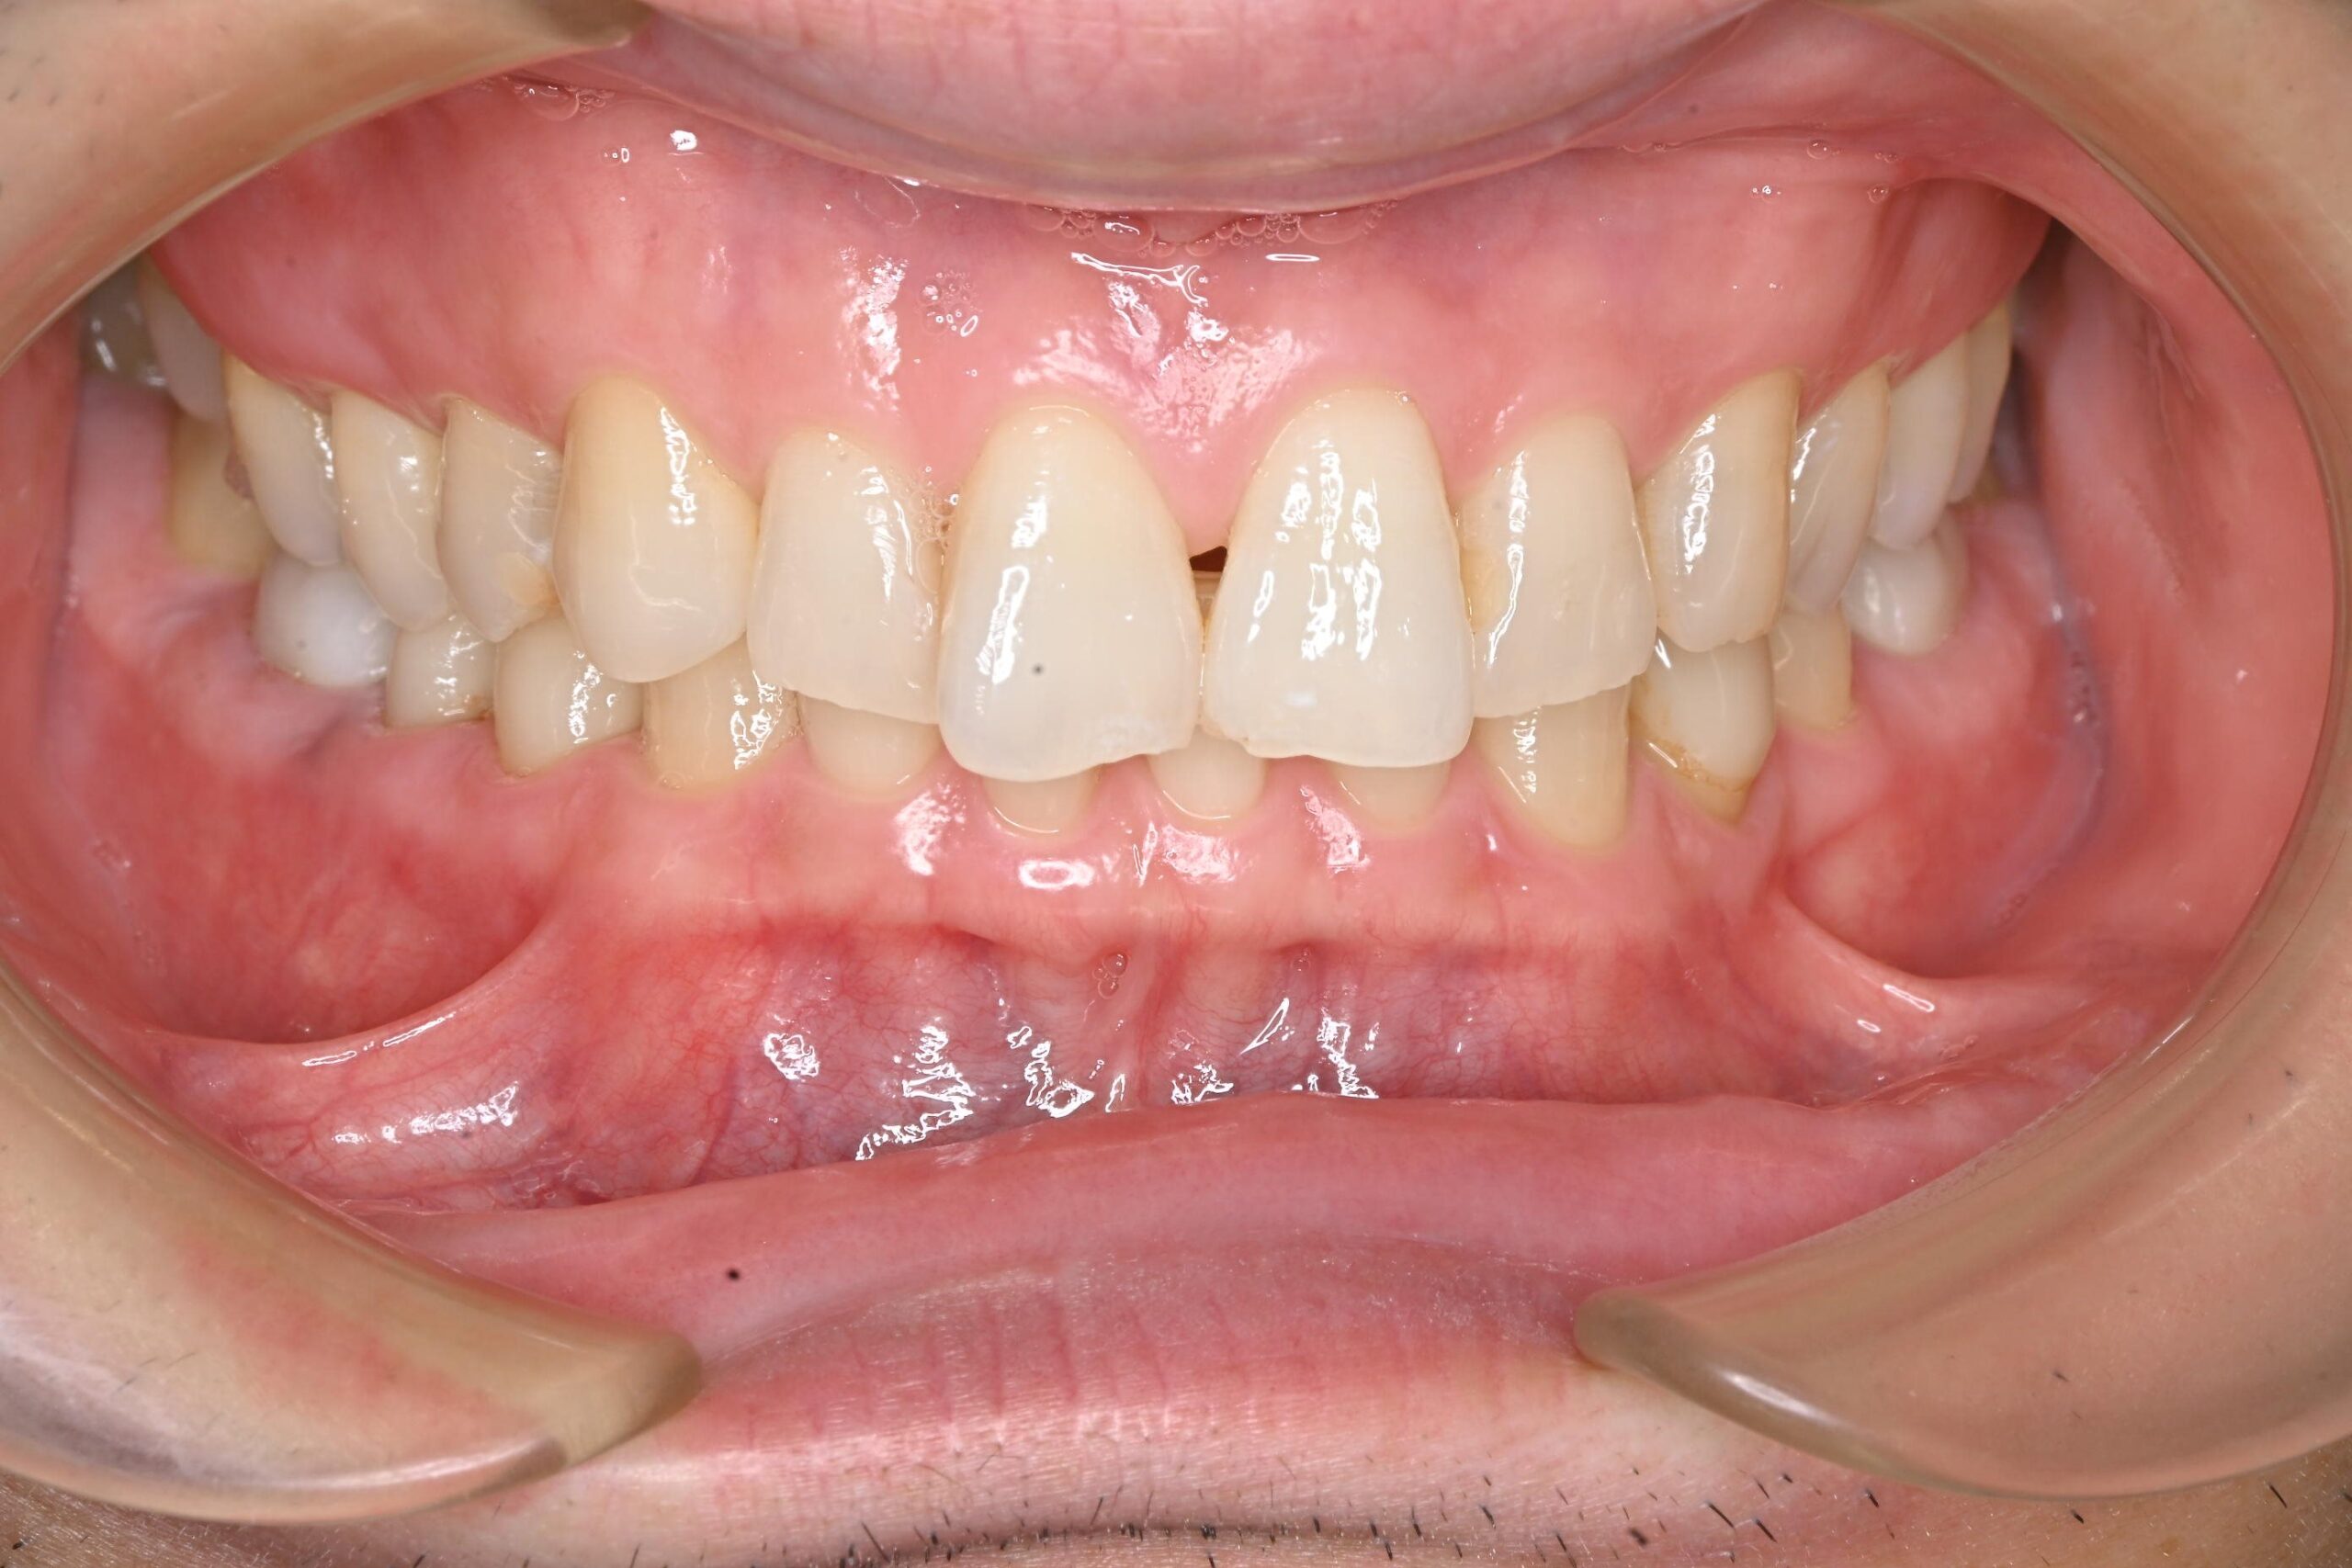

治療結果

全ての金属を非金属素材に置き換え、感染源も除去した結果、治療後は症状が落ち着いている状態が確認されました。 患者様はアレルギーやそれに伴う症状の悩みが大幅に軽減されたようで、非常に喜んでいただけました。

本症例では、金属アレルギーの懸念に加え、古い金属修復物の下に潜んでいた虫歯や感染源を全て取り除き、生体親和性が高く審美性にも優れた非金属素材に置き換えることができました。

患者様が長年抱えていたアレルギーや全身症状に関する悩みが軽減され、大変喜んでいただけたことは何よりでした。

After